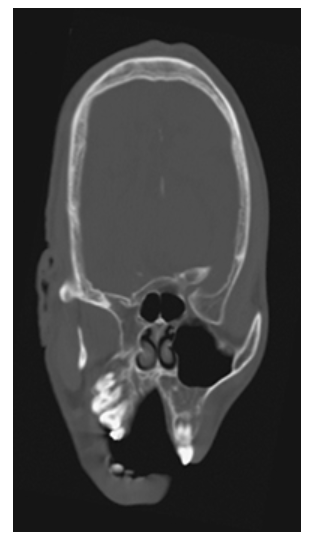

Crainosynostosis. Axial NECT shows elongation of the calvarium in the antero-posterior dimension and narrowing in the transverse dimension.

Crainosynostosis. Coronal NECT shows premature complete fusion of the sagittal suture.